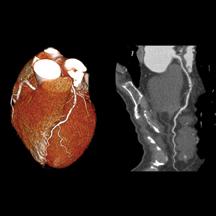

Get Ct Scan Calcium Score US. Specifically, it looks for calcium deposits in the coronary arteries that can narrow arteries and increase the risk of heart attack. This is not the stuff you get on your teeth, but a different kind found in your arteries.

Noninvasive Imaging Using Computed Tomography for Coronary ...

(the names given to the various kinds of cardiac ct scans can be confusing, but any ct scan used to measure coronary artery calcium is usually referred to simply as. Scanning time is often about 20 seconds, and radiation exposure is low. In july 2019 i summarized coronary calcium scanning with the humbly named the ultimate guide to the coronary artery calcium scan (score) circa 2019. Many acute cardiac events occur in previously asymptomatic individuals.